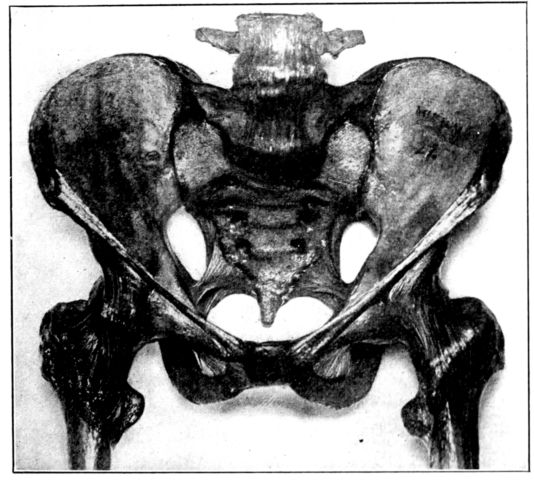

A. Normal female Pelvis.

B. Normal male Pelvis.

Fig. 1.—Normal Pelves. Note the broad, shallow, light construction of the female pelvis, A, as compared with the more massive male pelvis, B.

The normal male pelvis is deep, narrow, rough and massive as compared with the female structure (see Fig. 1.), and the angle of the pubic arch, formed by the two pubic bones, is deeper and more acute in the male than in the female skeleton.

The normal female pelvis, on the other hand, is light, broad, shallow, smooth and large, giving evidence of the infinite wisdom and skill that entered into constructing it for the high purpose it was designed to serve.